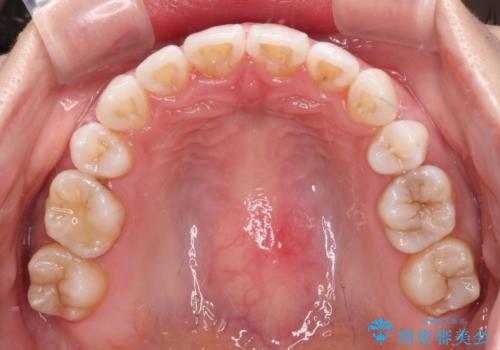

- 口元の突出感と口の閉じにくさを気にして来院された患者様です。

上下左右第一小臼歯4本を抜歯し、ワイヤー装置にて口元を引っ込めるよう矯正治療を行うこととしました。

2年~2年半が治療期間の目安でしたが、順調に治療が進み、1年9か月で満足のいく歯列となりました。